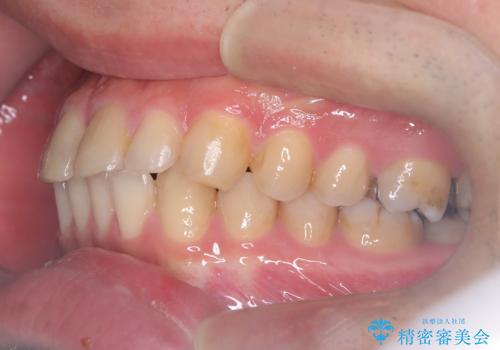

- 前歯の隙間と歯のデコボコを主訴にご来院された患者様です。

加えて、上下の奥歯が全く咬み合わないシザーズバイトの状態も認められました。

矯正検査の結果、非抜歯でインビザラインによる治療が可能と判断し、治療を行いました。

歯の隙間とデコボコ、シザーズバイトも改善され、咬み合わせや見た目が整い、患者様にも大変ご満足いただけました。